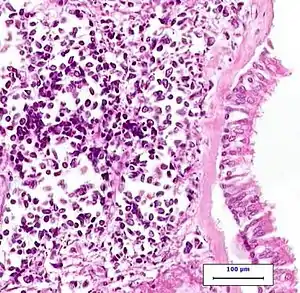

| A CT scan of limited-stage small cell lung carcinoma | |